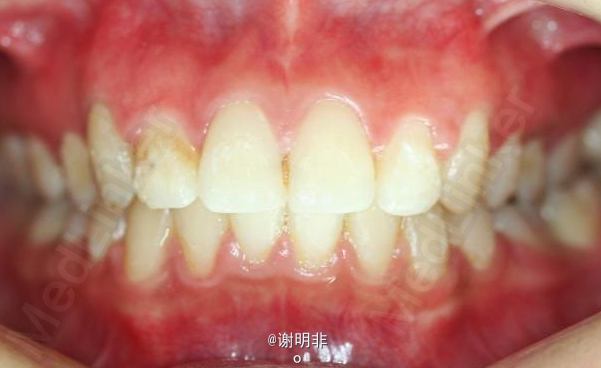

又一例不对称拔牙

牙弓狭窄,牙列拥挤

不对称拔牙